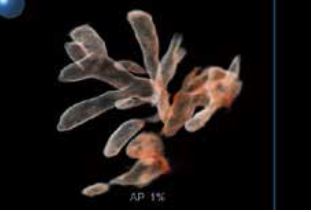

Shadow Glass - це новітня технологія візуалізації, яку можна застосувати до зображень, отриманих за допомогою Smart Sensor 3D. Цей інноваційний метод відображення дозволяє спостерігати внутрішні структури, оскільки він використовує два різні фільтри для створення напівпрозорого об'ємного зображення. У порівнянні зі звичайними 3D-зображеннями, Shadow Glass дозволяє легше спостерігати за цілісними структурами. У випадку плоду Shadow Glass дозволяє чітко роздивитись органи відносно загальної анатомії.

Рисунок 2. Схема роботи Shadow Glass

a) Візуалізація об'єму

б) Яскравість

в) Shadow Glass

Рисунок 3. Візуалізація плоду з використанням візуалізації об'єму (a), яскравості ( б) та Shadow Glass ( в).